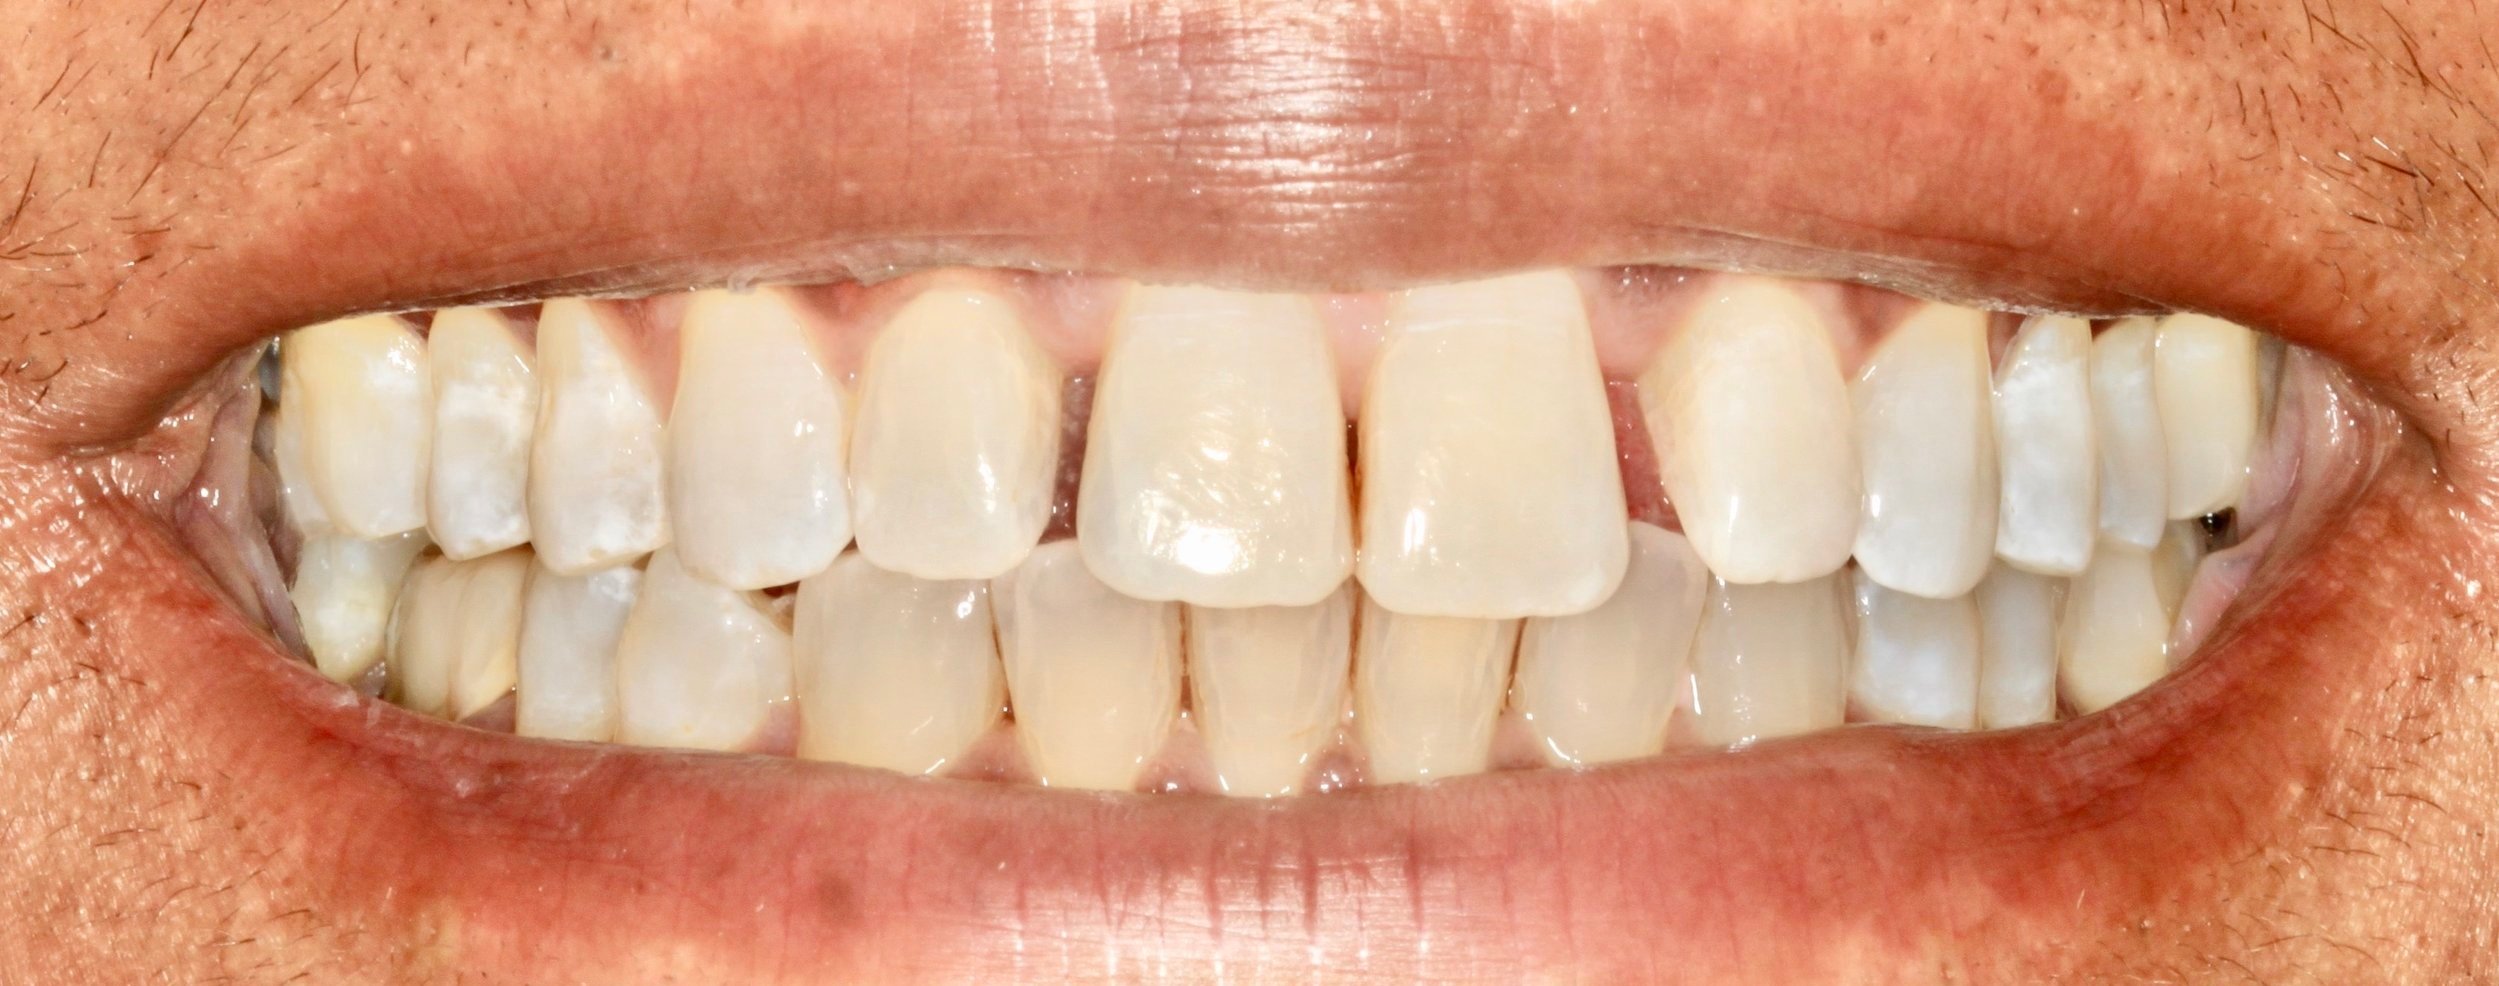

Before

After